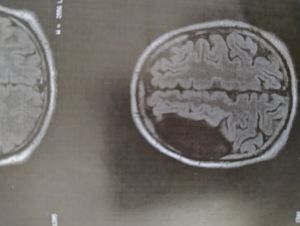

Cirurgia cérebral, a um ano na espera do SUS, mas sem sucesso, perca da visão do lado direito devido a compressão da massa.

Massa cerebral em crescimento, dores diariamente, já perdeu a visão direita toda praticamente.